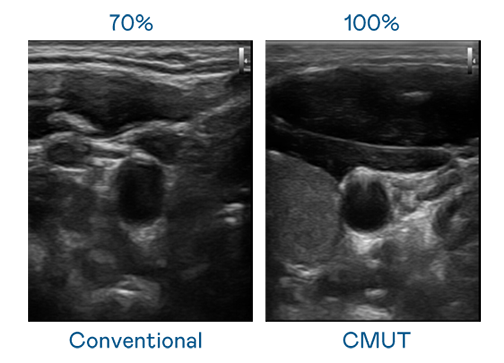

CMUT 技術是一種用電容式微機電元件來產生超音波訊號的技術。與傳統 PZT 壓電式技術相比,CMUT 頻寬增加 30%,更寬頻的超音波訊號讓影像解析度大幅提升,是實現高影像品質醫療超音波掃描、促進精準醫療發展的關鍵技術。

超音波影像的解析度高低,首先取決於探頭能發出的訊號頻寬。赢多多 CMUT 可提供高清晰的超音波訊號,提供高頻寬、高靈敏度、影像紋理細節更高的超音波影像,協助醫護人員縮短影像判讀時間及利用精準的醫療影像進行診斷。